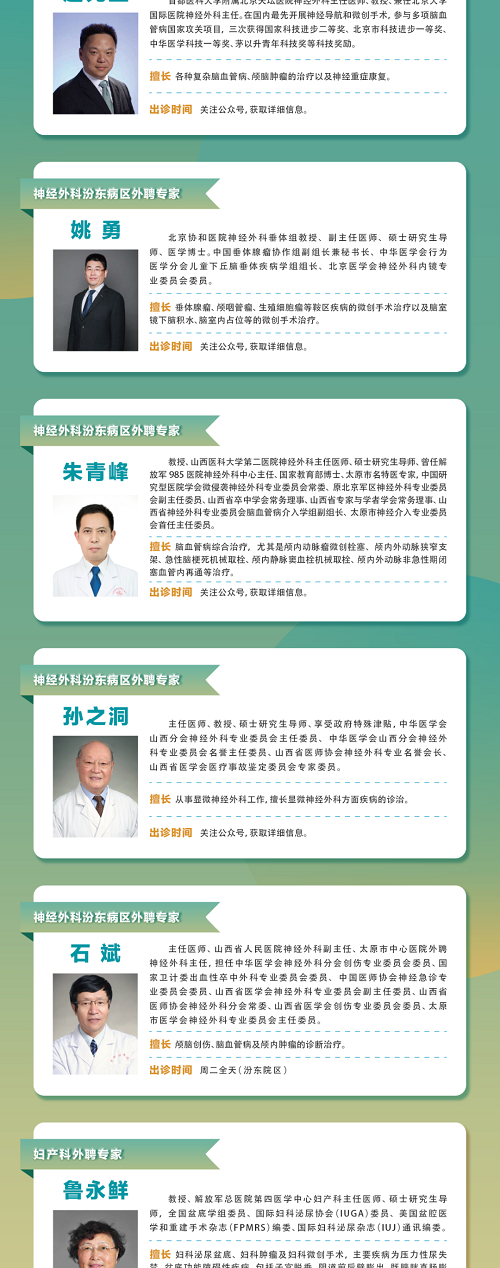

學科帶頭人

林樹忠

骨科汾東三病區主任、副主任醫師、碩士、運動醫學專業學組組長、骨關節疾病專家。

擅長四肢關節運動損傷的微創治療,如半月板成形、韌帶修補、軟骨移植、前后交叉韌帶重建、肩袖損傷修補、髖關節撞擊綜合征、踝關節撞擊綜合征、滑膜皺襞綜合征等微創手術治療;輕中度膝關節骨性關節炎的保膝治療,重度髖膝骨性關節的人工關節置換治療。

聯系電話:13503509864

專家門診

林樹忠副主任醫師:周一、周四上午

普通門診

何君仁主治醫師門診:周三上午、周五下午

劉文琦主治醫師門診:周二下午

杜晉強主治醫師門診:周四下午

咨詢電話

0351-5656547

門診地址

府城院區

太原市中心醫院府城院區:山西省太原市杏花嶺區解放路東三道巷1號。

交通指南:乘坐25路、3路、615路公交車至北肖墻壩陵北街口(征兵大廈),向西100米;乘坐610路(臨)、820路、820支路(臨)、829路(臨)公交車至解放路市中心醫院站,東二道巷向東200米即到。

汾東院區

太原市中心醫院汾東院區:山西省太原市小店區汾東大街256號,汾東大街與太茅路交叉路口東南角。

交通指南:乘坐公交車906,306路公交,賈家寨村下車可達。